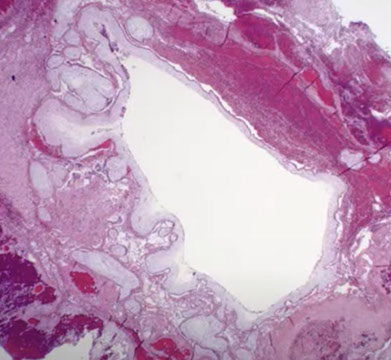

Partial Hydatidiform Mole (PHM)

Gross: mix of vesicular and normal villi

Micro: mix of edematous and normal villi

- villous scalloping (irregular shape with trophoblast villi goes into villous stroma)

- do not develop uniformly hydropic villi, giving it a biphasic population of hydropic villi mixed c smaller fibrotic immature villi

- have stromal trophoblastic pseudoinclusions

- circumferential trophoblast proliferation less pronounced than in complete moles

- early partial mole suspected if some villi are dilated and not others, and borders usually more scalloped than late-term partial moles

PHM gross. Hard to see the swollen cysts [2]

PHM. Intermixed biphasic population of villi by size. Proposed stringent threshold for villous enlargement >2.5 mm

PHMs have complex, irregular shapes in larger villi

PHMs have inclusions that reflect the shape complexity

PHMs with scattered cavitation of larger villi

PHM trophoblastic hyperplasia, proliferation commensurate to size and "tagging". Proliferation is just enough to keep up with the size of the villi

PHM fetal blood can commonly be seen, as well as an amnion and chorion (not pictured here)